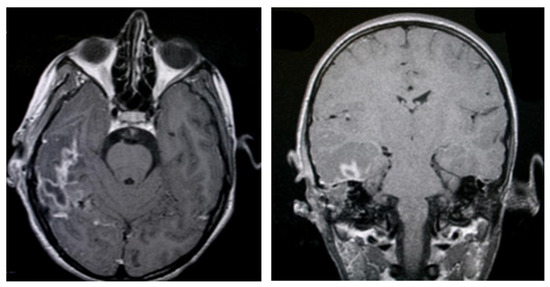

3.1.2. Computed Tomography and Magnetic Resonance Imaging

| CT Aspects | Number of Patients | Percentage |

|---|---|---|

| Fluid accumulation | 168 | 100% |

| Osteolysis | 152 | 90.47% |

| Osteocondensations | 128 | 76.19% |

| Cholesteatoma | 48 | 28.57% |

| Exocranial extensions | 48 | 28.57% |

| Intracranial extensions | 24 | 14.28% |

| Changes to the external auditory canal | 68 | 40.47% |

| Ossicular chain damage | 144 | 85.71% |

| MRI Aspects | Number of Patients | Percentage |

| Edema | 128 | 100% |

| Cholesteatoma | 40 | 31.25% |

| Exocranial extensions | 40 | 31.25% |

| Intracranial extensions | 32 | 25% |

| Inner ear damage | 20 | 15.62% |